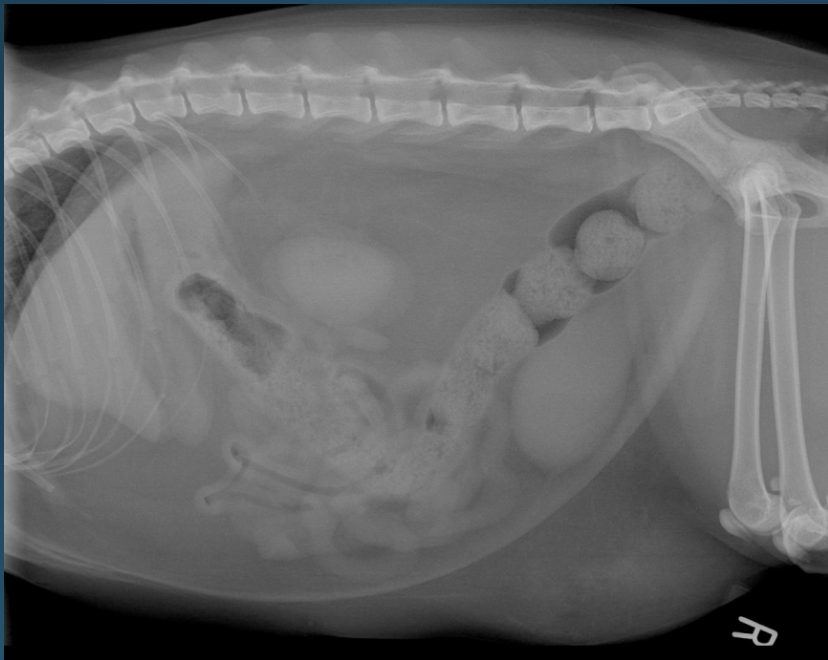

What is shown in this image?

normal abdomen in an obese cat